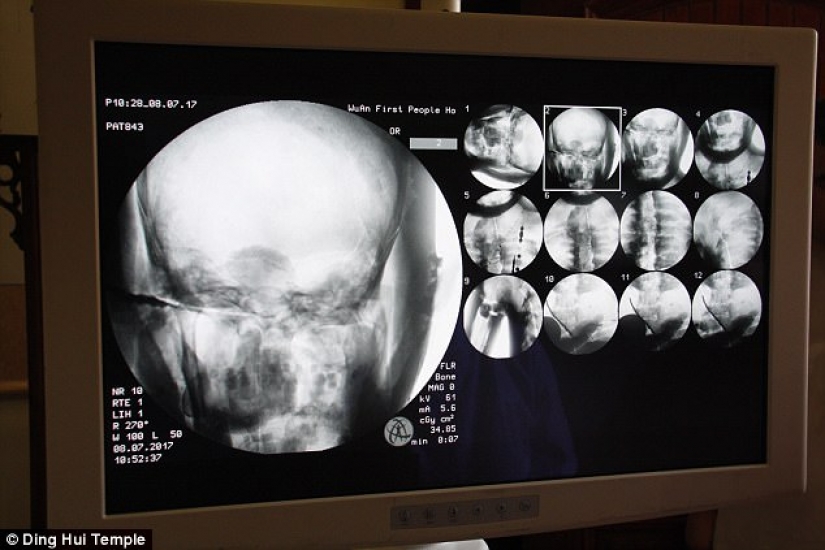

Por Pictolic https://www.pictolic.com/es/article/una-momia-milenaria-de-un-monje-budista-tiene-un-cerebro-y-un-esqueleto-preservados-en-perfecto-estado.htmlEl cuerpo momificado de un monje budista de mil años todavía tiene los huesos y el cerebro intactos. Esto fue revelado por una tomografía computarizada.

El descubrimiento se realizó después de que los restos dorados del Maestro Ci Xian se sometieran a un examen médico en el Templo Dinghui en el norte de China.

La tomografía computarizada se realizó el 8 de julio. La gente se sorprendió cuando los médicos dijeron que el esqueleto y el cerebro de Ci Xian estaban en perfectas condiciones. "Podemos ver que sus huesos están tan sanos como los de una persona normal: la mandíbula superior, los dientes superiores, las costillas, la columna vertebral y todas las articulaciones están perfectamente conservadas. Esto es increíble", dijo el Dr. Wu Yongqing.